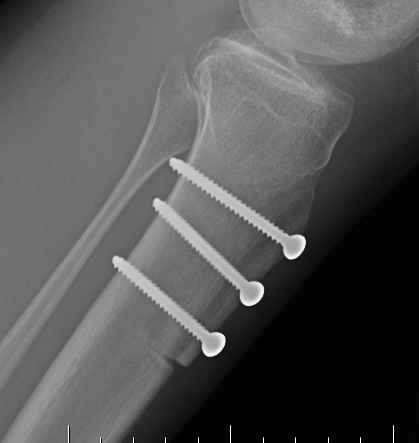

Tibial tuberosity osteotomy (TTO)

- systematic review of patients with PFJ chondral lesions

- compare isolated ACI versus combined ACI and TTO

- better outcomes with ACI / TTO